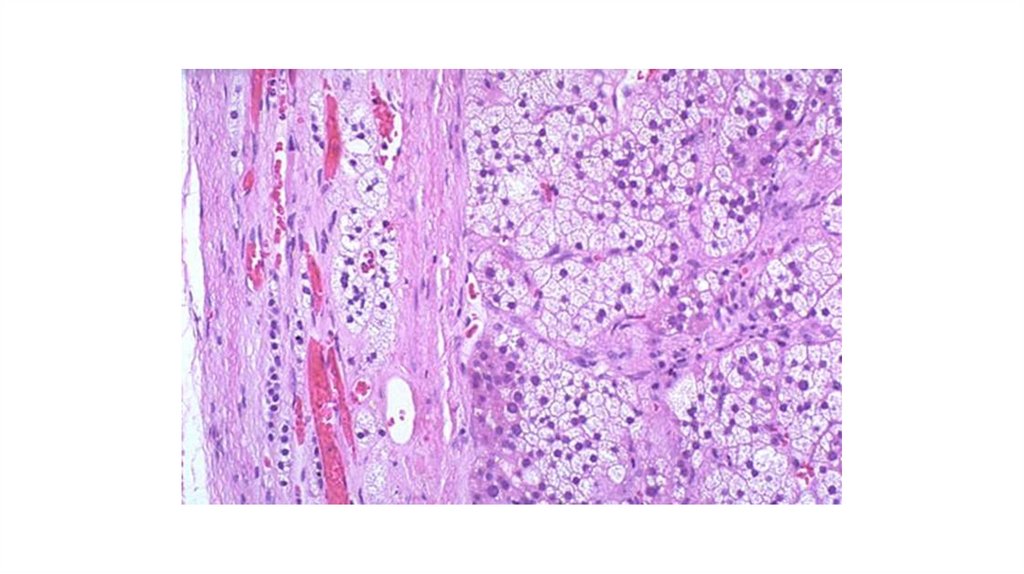

10. Печень при миелолейкозе

11. Пигментный невус